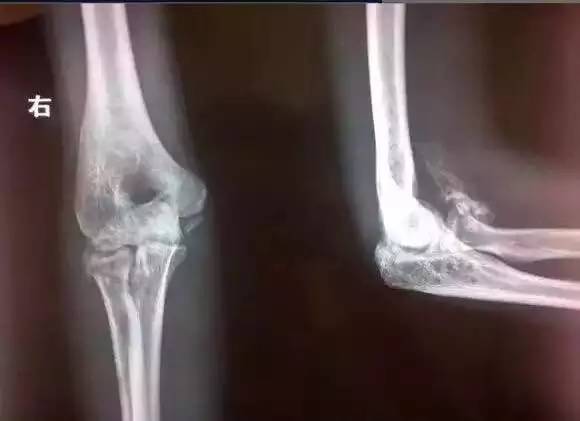

肘关节骨折是临床较常见的疾病,肘部常见骨折为肱骨髁上骨折、髁间骨折、外上髁骨折、内上髁骨折、尺骨鹰嘴骨折、桡骨头骨折等,临床资料显示在45000例骨伤病例中肘关节损伤占14%,占所有骨关节损伤的首位。肘关节由肱骨远端、尺骨、桡骨近端构成、包括肱尺关节、肱桡关节和上尺桡关节。由于肘关节的解剖特性,损伤后易发生功能障碍,也就是我们平常说的活动度变小。那么肘关节功能障碍后经康复治疗关节活动度练不开的原因是什么呢?

1. 骨化性肌炎

(图片来自网络)

骨化性肌炎是一种以纤维性、软骨或骨性化生为特征的局部反应性病变。通俗来说就是关节周围该是软组织的地方长成骨头了,因为骨头不具有软组织的弹性与延展性所以对关节活动度的影响就显而易见了。这种改变是不可逆的,也就是说一旦发生控制住骨化不再生长就已经是很好的结果,想让骨化消失现在还没有已知的方法。肘关节是最易发生骨化性肌炎的关节,膝关节次之。确切的发病机制还不清楚,损伤严重、体质容易骨化、再加上不正确的过度的康复治疗和练习就会造成骨化性肌炎这种并发症。我们在对肘关节进行康复治疗的时候一定要预防骨化性肌炎的发生即预防是首要的,如果不幸发生了骨化性肌炎那么:1.不可以做肘关节周围肌肉的按摩。有的患者觉得练完关节后按摩可以放松肌肉就加大力度进行肌肉按摩,这种做法是不正确的。练完关节后关节周围肯定存在轻微的损伤与充血,这个时候再进行肌肉按摩反而加重这种炎症反应促进骨化的生长。2.一旦发生骨化性肌炎不可以做任何有热效应的理疗,包括蜡疗、磁疗、中药蒸汽浴等等。热作用在促进血液循环的同时也会促进骨化的活动。3.练角度时切不可“太狠”,有的患者在练角度时疼的撕心裂肺,“哇哇”大哭,康复治疗师一边鼓励患者坚持一边“掰胳膊”。这种大强度的关节刺激同样会加大骨化的进展。骨化性肌炎的患者一定要注意康复治疗的强度与治疗量,量太大对关节的刺激就大。治疗强度的掌握可以以疼痛为参考,疼痛不要超过4分。4.及时冰敷,冰敷可以减少损伤后局部炎性物质的积累,减轻炎性反应。